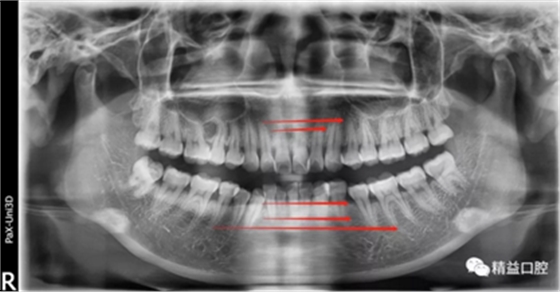

矯正前全口曲斷片

從片子上可以清除看到,上牙門牙牙根吸收非常厲害。